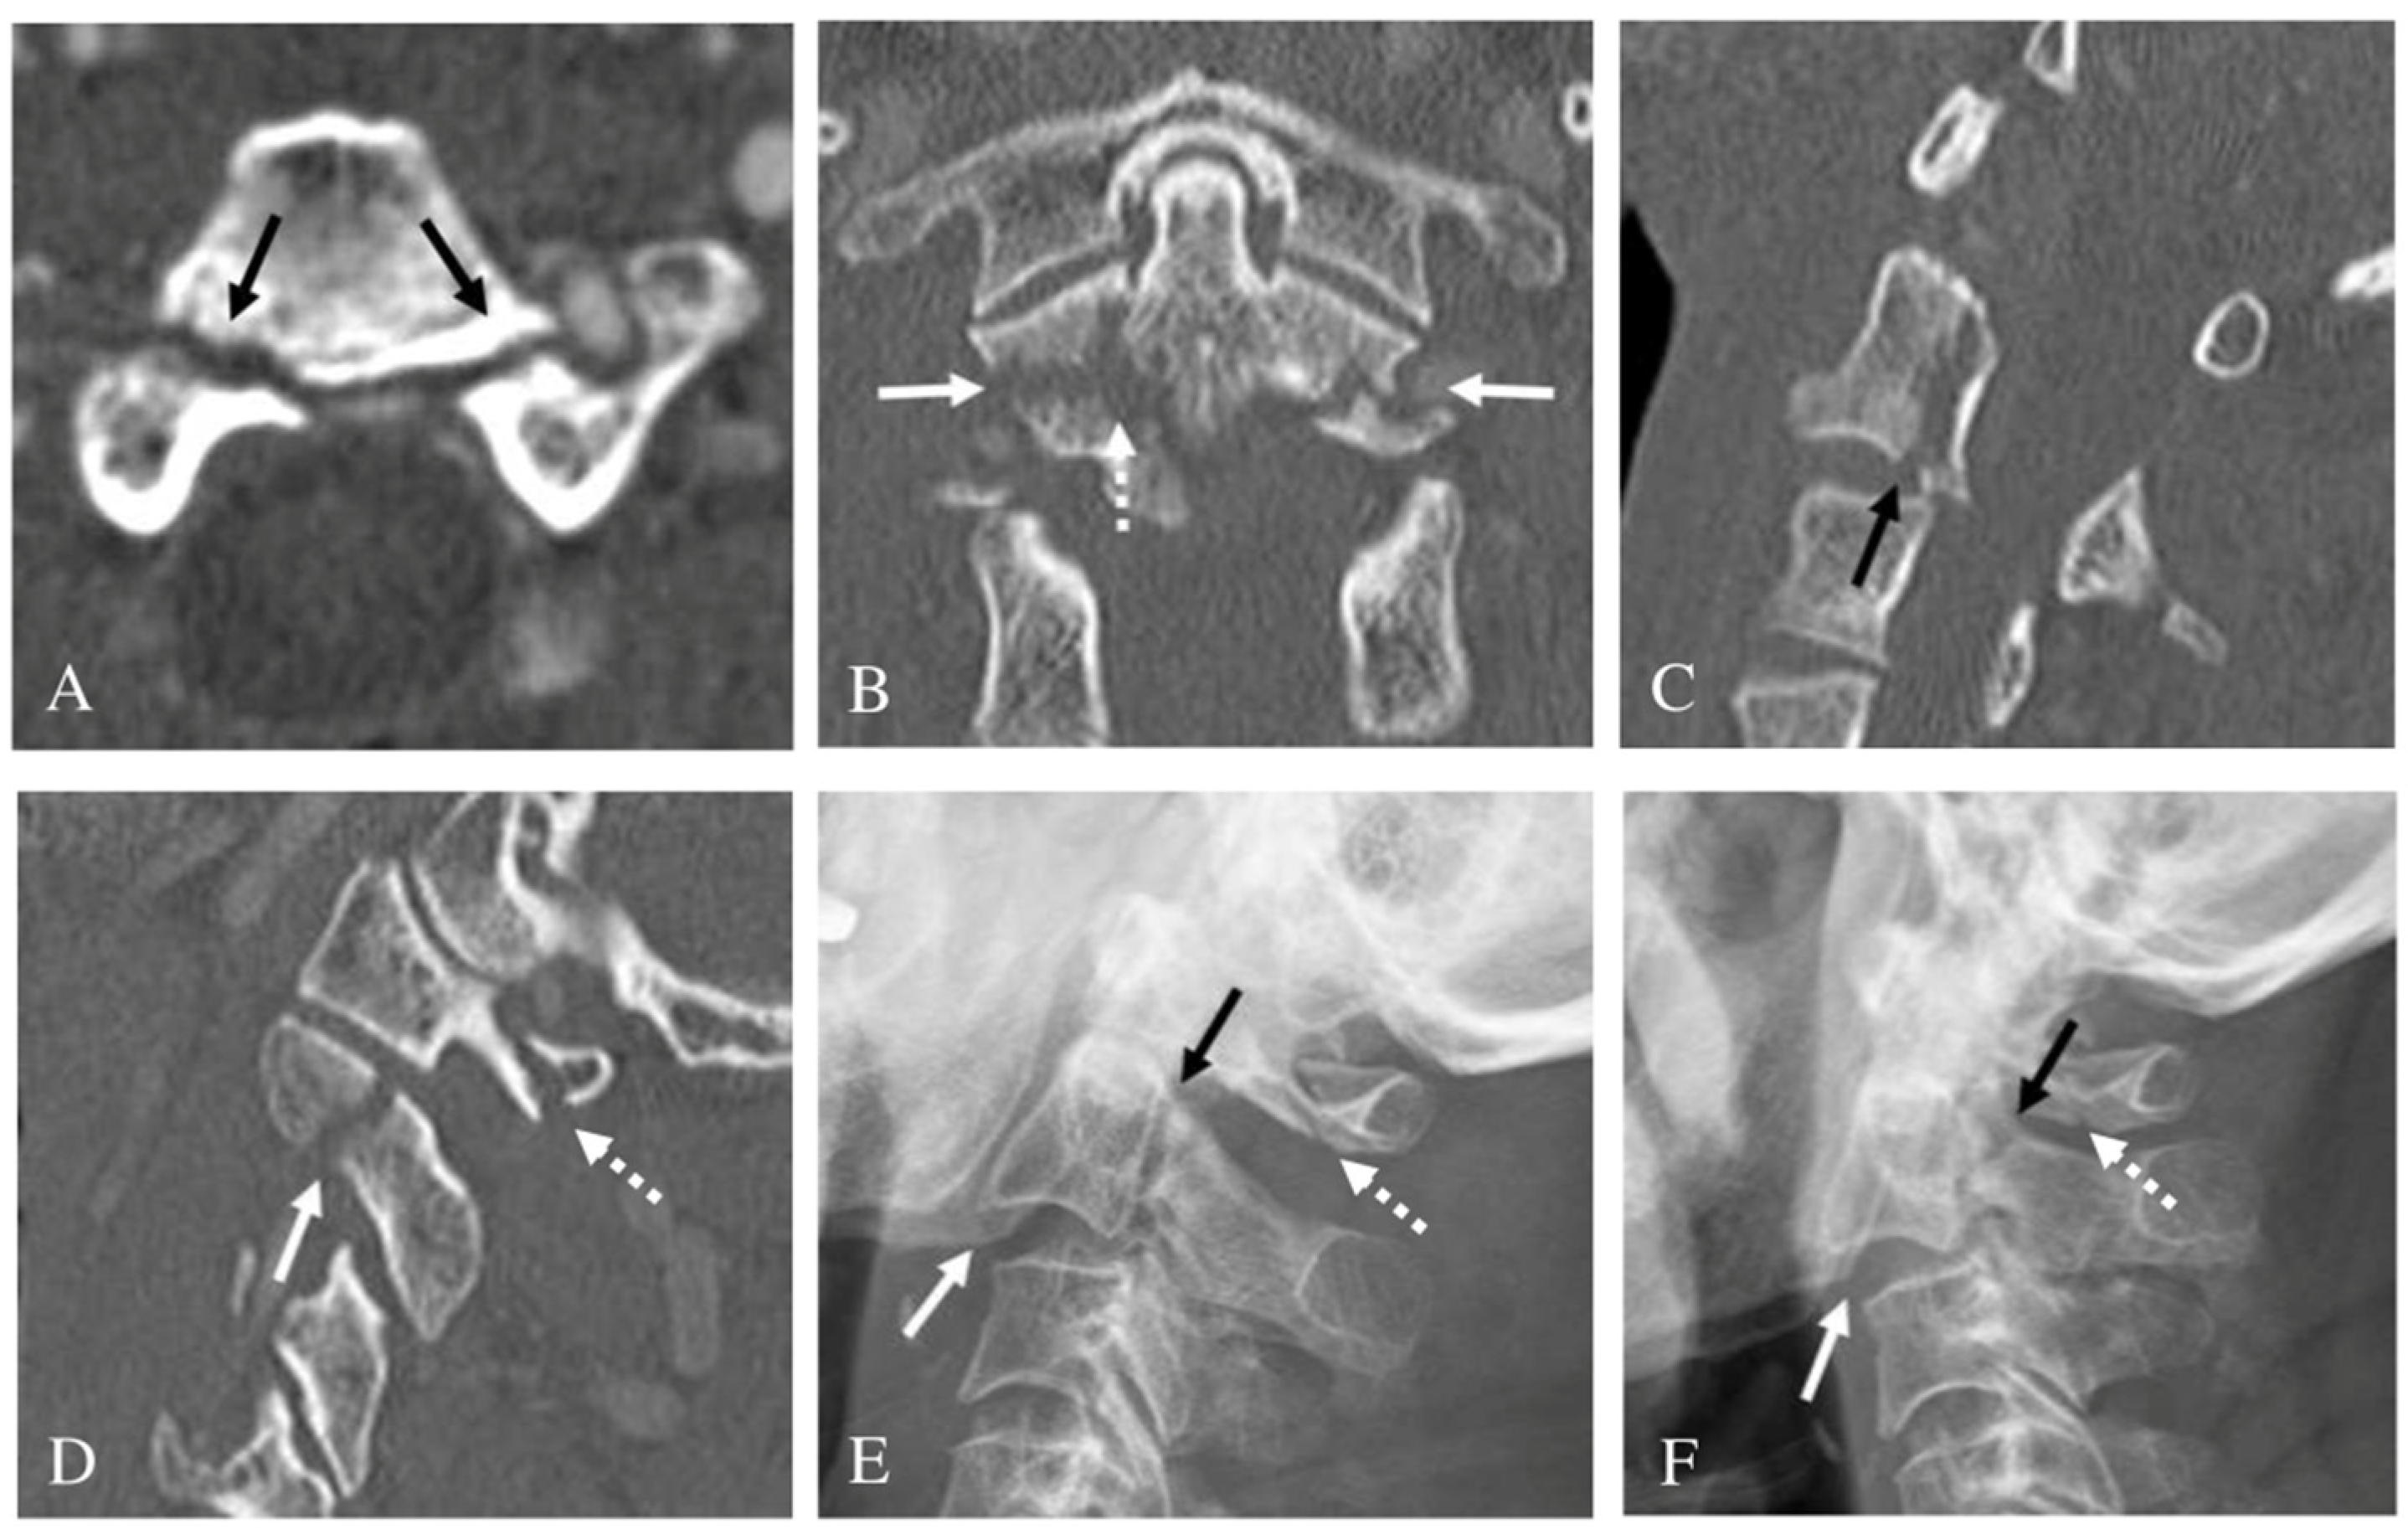

3.3. Bilateral Pedicle Fracture

3.4. Treatment Outcomes